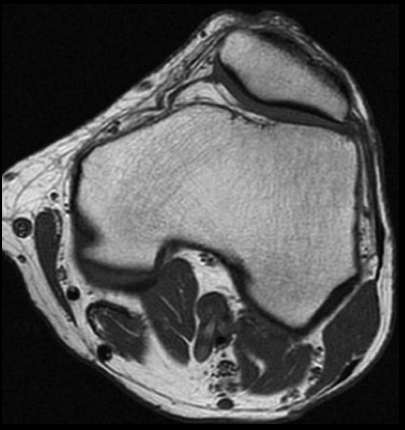

SE T1 AXIAL

3. Para confirmar los hallazgos de la angioTC de extremidades inferiores, se realizó RM de rodilla izquierda. ¿Qué hallazgo se observa en la secuencia axial SE T1?

- A. Aneurisma poplíteo trombosado.

- B. Quiste adventicial en la pared de la arteria poplítea.

- C. Banda muscular anómala rodeando a la arteria poplítea.

- D. Exóstosis de tibia comprimiendo la arteria poplítea.

- E. Flap intimal intraluminal.